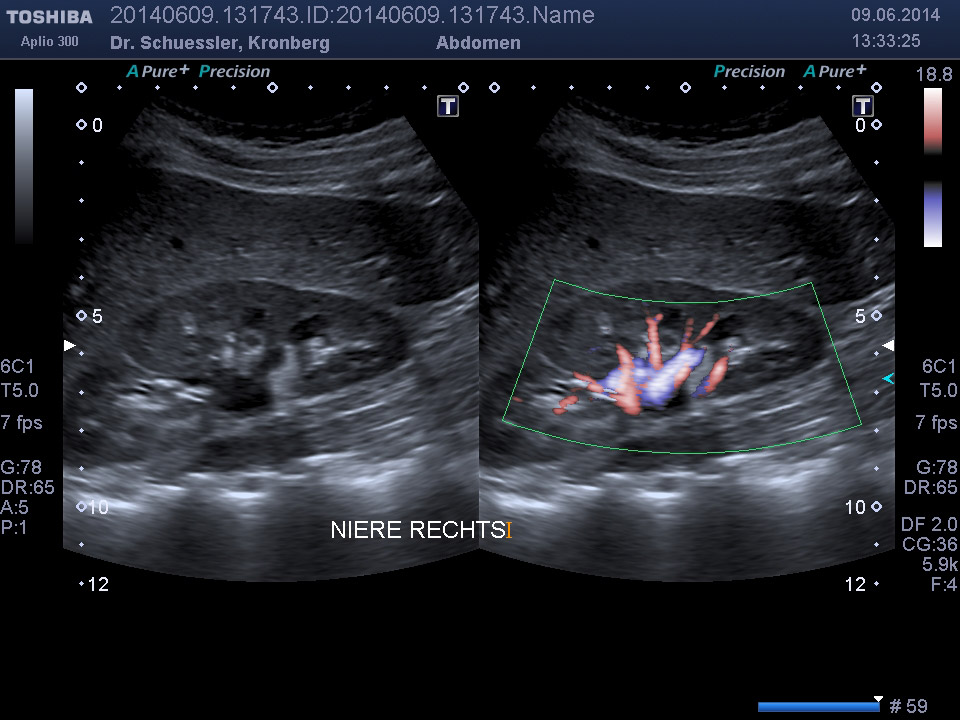

Durch Ergänzung des farbkodierten Duplexverfahrens läßt sich die Durchblutungssituation der Bauchorgane erfassen.